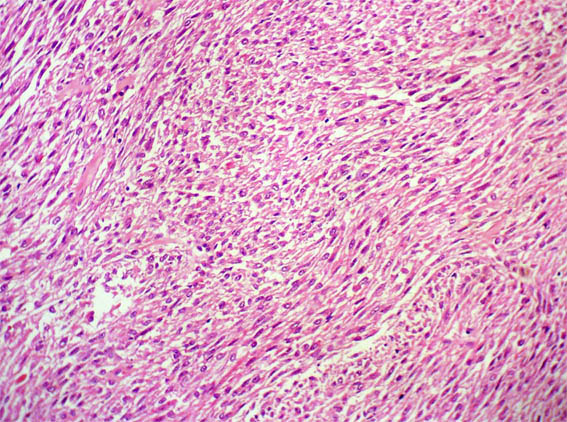

Figura 2.

H&E, X200.